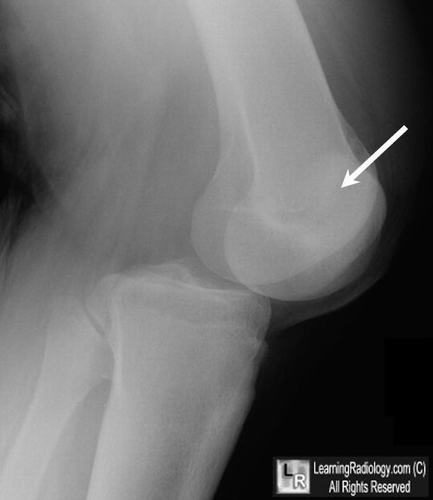

Trật khớp là hiện tượng khớp 2 khớp nối nhau bị so le không còn nằm ở vị trí như ban đầu. Bệnh thường xảy ra khi cử động mạnh hay lặp lại động tác nhiều lần với cường độ cao,.. Trật khớp cần điều trị kịp thời và để bệnh nhanh chóng hồi phục thì chăm sóc vết thương sau khi điều trị trật khớp là điều vô cùng quan trọng.

Trật khớp là hiện tượng khớp 2 khớp nối nhau bị so le không còn nằm ở vị trí như ban đầu.

Triệu chứng khi bị trật khớp

- Biến dạng khớp hoặc khớp có thể nhô ra ngoài

- Sưng nề hoặc bầm tím

- Đau nhiều

- Không cử động được

- Cảm giác kiến bò hoặc tê bì ở gần nơi tổn thương – ở bàn chân trong trường hợp trật khớp gối hoặc ở bàn tay trong trường hợp trật khớp khuỷu.